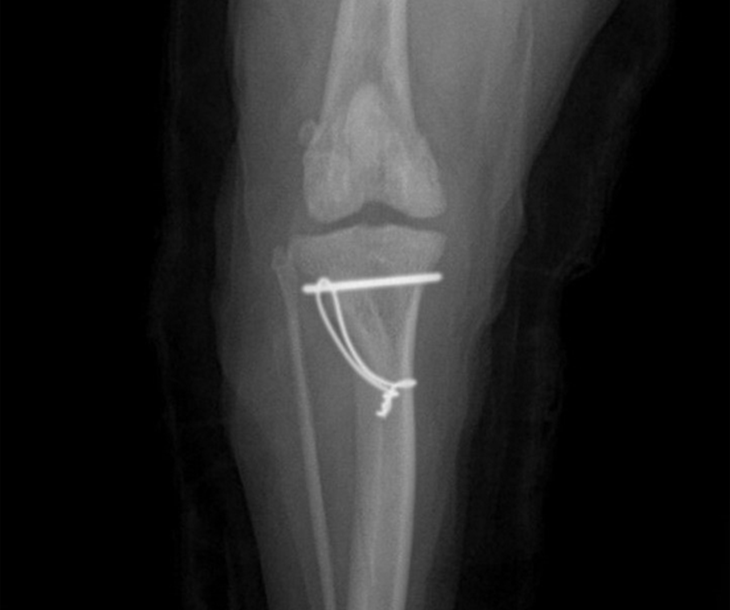

슬개골 탈구

십자인대 파열은 개의 무릎 관절에서 발생하는 일반적인 부상 중 하나로,특히 노령 개에서 더욱 흔하게 발생합니다. 노화 과정은 십자인대의 결합 조직을 약화시켜, 일상 활동 중에도 파열이 발생할 수 있게 만듭니다. 이러한 상황은 관절의 안정성 손실,통증,그리고 장기적으로는 관절염으로 이어질 수 있는 심각한 문제를 초래합니다.